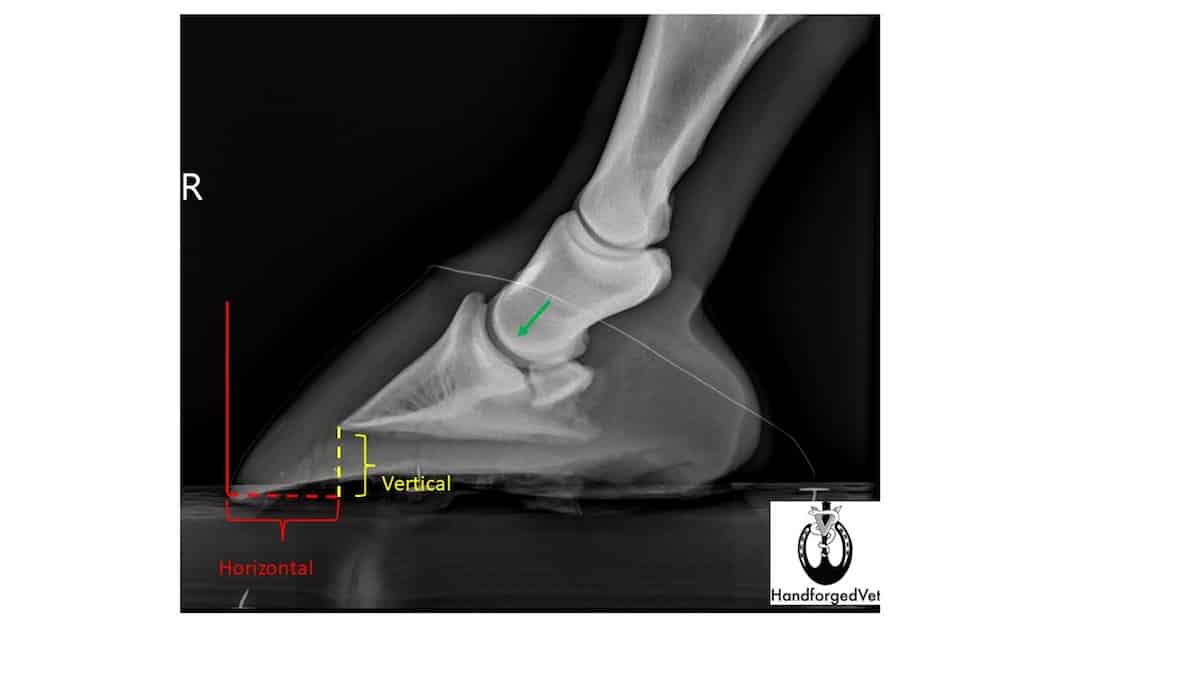

A negative palmar angle (the white dotted line) forms when the back portion of the coffin bone is closer to the ground than the front portion. Courtesy Dr. Adam Pendleton

Another all-too-common pathology in Thoroughbreds is the long-toe, low-heel hoof. It’s most often accompanied by the dreaded negative palmar angle (NPA). Diagnosed via radiographs, this angle occurs when the back portion of the coffin bone is closer to the ground than the front portion. This puts an immense amount of pressure on the supporting soft tissue structures of the heel, including the deep digital flexor tendon, the collateral ligaments and the navicular apparatus.

As stated, radiographs are the definitive way to diagnose a horse with an NPA. Furthermore, diagnostic images give the farrier incredibly important information on just how much they can trim. “You can’t see in the foot — none of us have X-ray vision,” says Balasar.